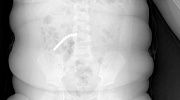

30 декабря пациентке планово выключили из кровотока оставшиеся две проблемные области. Хирурги установили клипсы через один доступ, что минимизировало травматичность и устранило угрозу кровоизлияний. 3 января этого года женщину выписали из больницы.